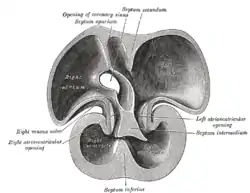

Interior dorsal half of heart of nearly 5 weeks old human embryo. (Labeled as 'septum inferius') | |

The ventricular septum is directed obliquely backward to the right and curved with the convexity toward the right ventricle; its margins correspond with the anterior and posterior longitudinal sulci. The greater portion of it is thick and muscular and constitutes the muscular interventricular septum. Its upper and posterior part, which separates the aortic vestibule from the lower part of the right atrium and upper part of the right ventricle, is thin and fibrous, and is termed the membranous ventricular septum.

The muscular part of the interventricular septum derives from the bulboventricular flange which is developed due to differential growth of primitive ventricle and bulbous cordis. Membranous part has a neural crest origin which connects the upper free margin of the bulboventricular flange and anterior and posterior endocardial cushions of atrio ventricular canal. It also gets attached to lower border of spiral septum or the aorticopulmonary septum.

In the final stages of the heart development, the interatrial septum aligns in the same plane as the interventricular septum. The gap between the interatrial septum and interventricular septum forms the membranous part of interventricular septum. [3]